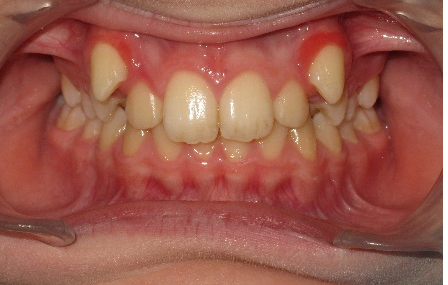

В полости рта: смыкание первых моляров по дистальному типу. Сужение зубных рядов в боковых отделах. 13 и 23 - вестибулярное и супраположение с дефицитом места в зубном ряду на величину ширины коронки клыка. Глубокая резцовая окклюзия.(рис.2.)

Рис.2.Смыкание зубных рядов пациента А. до лечения и окклюзионный вид.